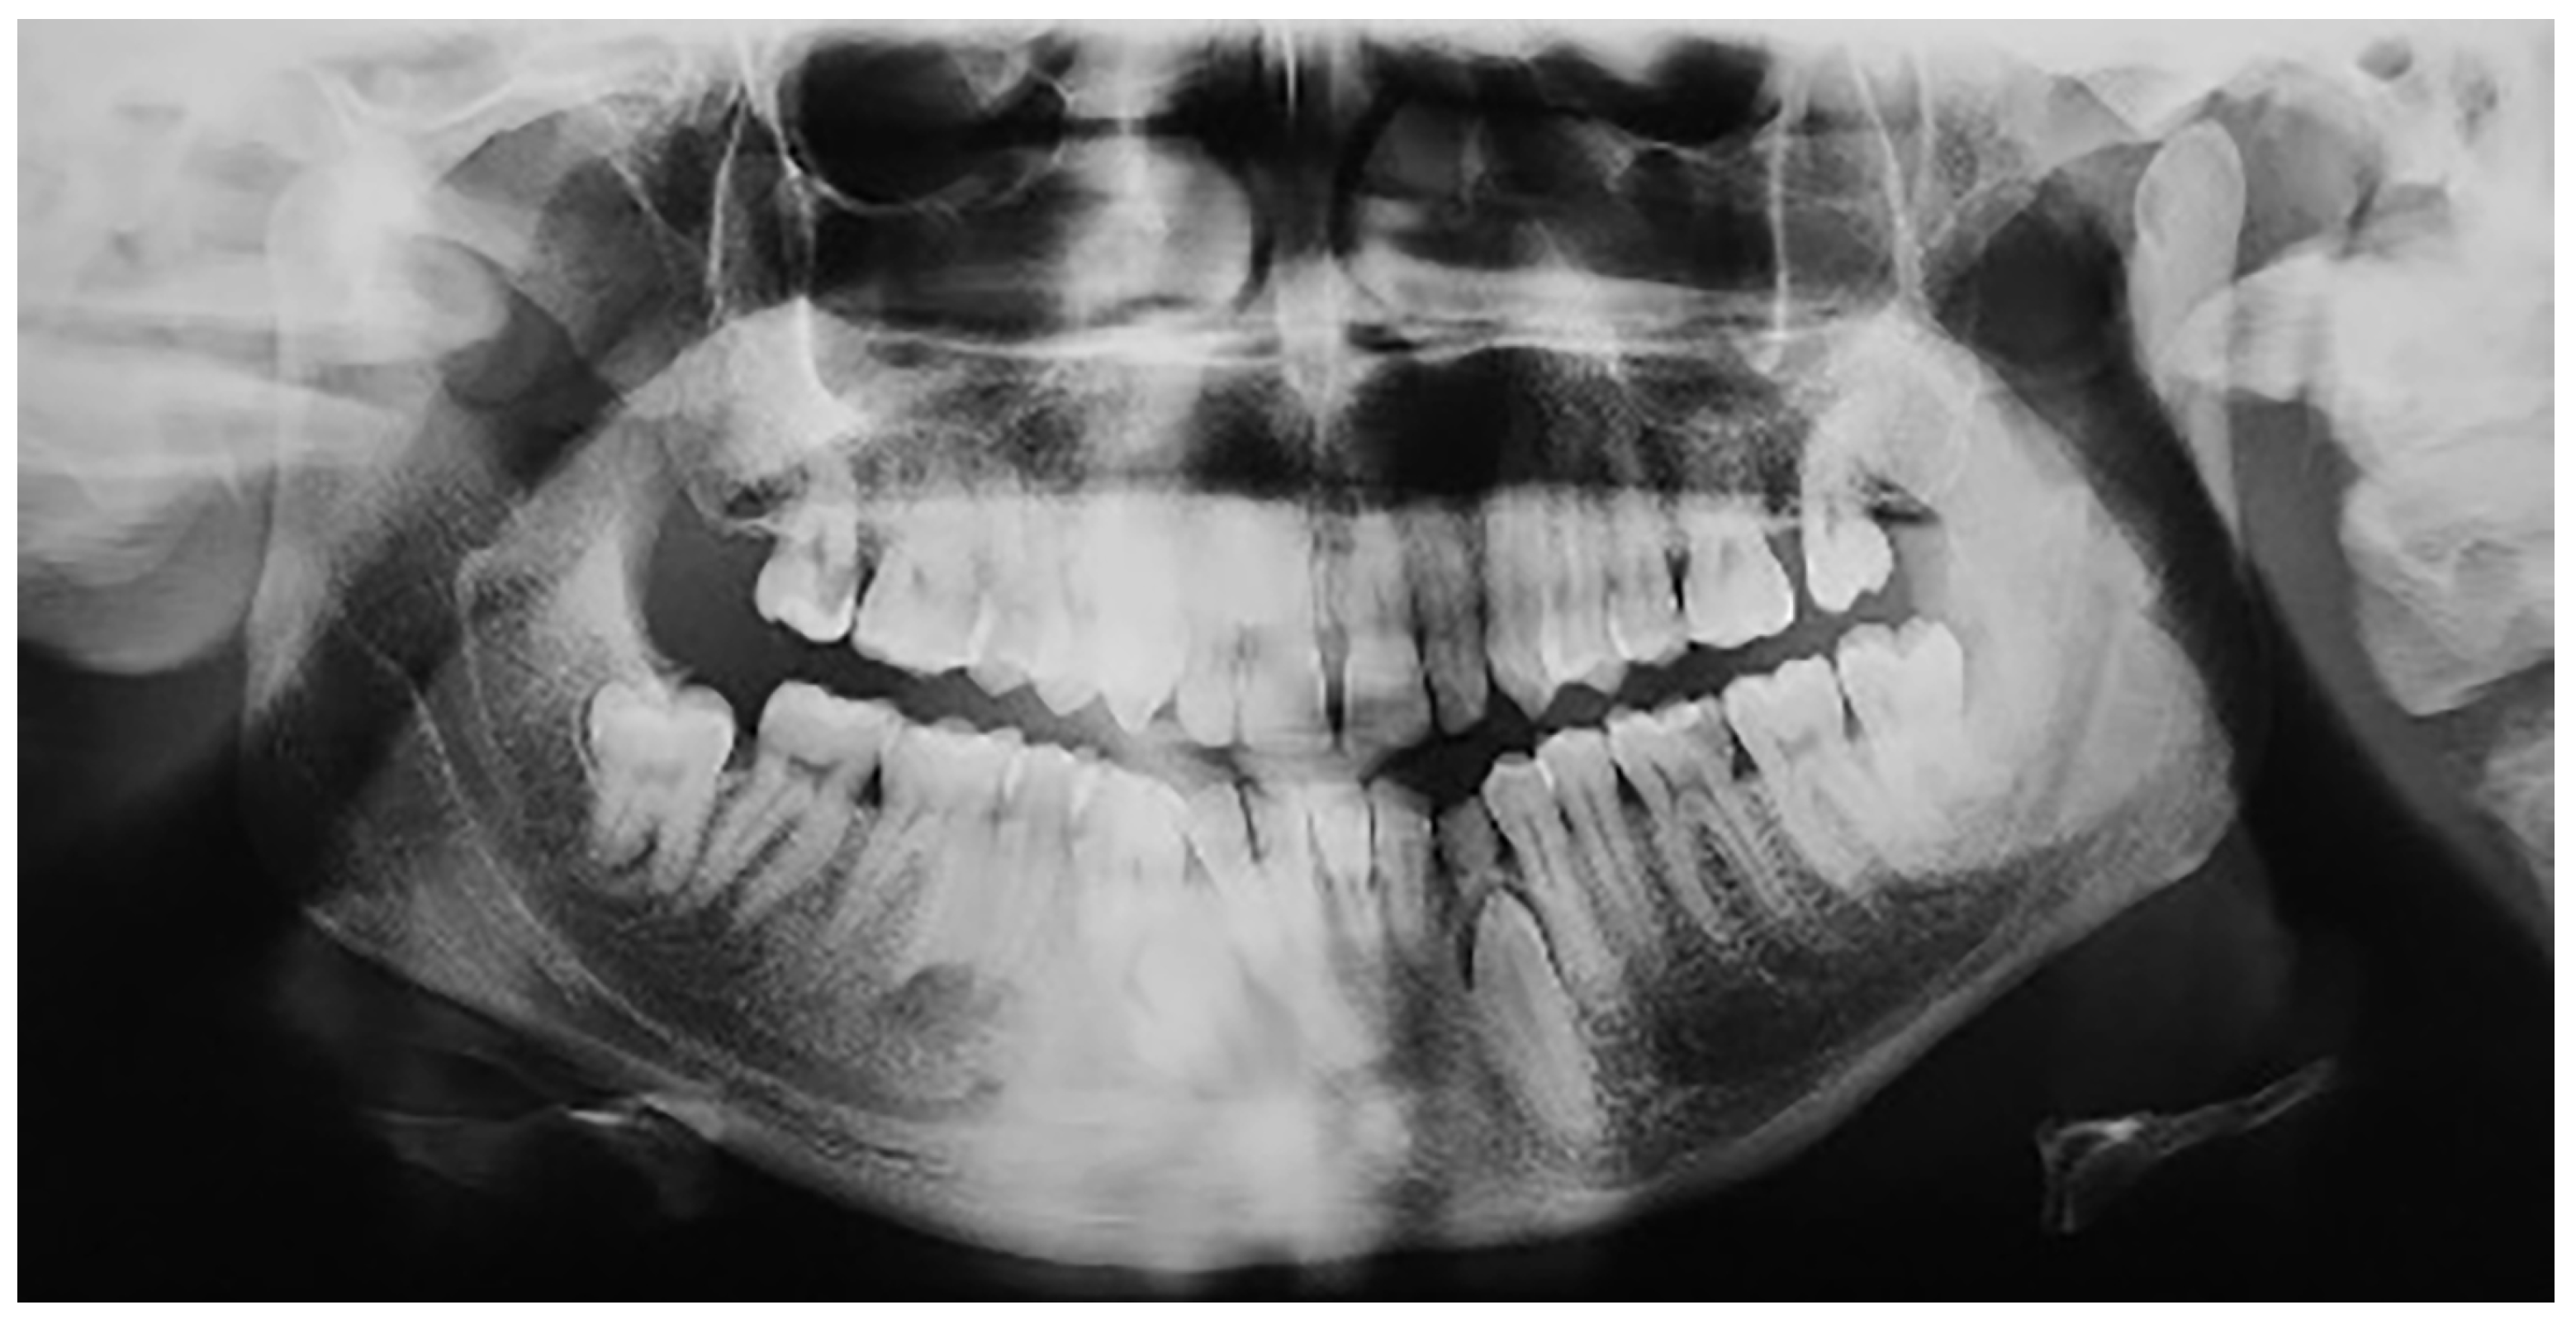

Transmigrated mandibular canines were classified according to Mupparapu’s classification [19]. Mupparapu used five criteria to classify the transmigrated mandibular canines into five types. This classification was based on their migratory pattern, the inclination of the longitudinal axis of the canine, the final position inside the mandible, and the relation of the canine crown with adjacent teeth, the midline, and the contralateral erupted canine (Figure 1) [19].

Figure 1.

Diagrammatic representation of the 5 patterns of transmigration, with a retained deciduous right mandibular canine according Mupparapu.

Type 1: the canine is positioned mesioangularly across the midline, labial or lingual to the anterior teeth, and the crown portion crosses the midline.

Type 2: the canine is impacted horizontally near the inferior border of the mandible below the apices of the incisors.

Type 3: the canine has erupted either mesially or distally to the opposite canine.

Type 4: the canine is horizontally impacted near the inferior border of the mandible below the apices of either premolars or molars on the opposite side.

Type 5: the canine is positioned vertically in the midline, with the long axis of the tooth crossing the midline.